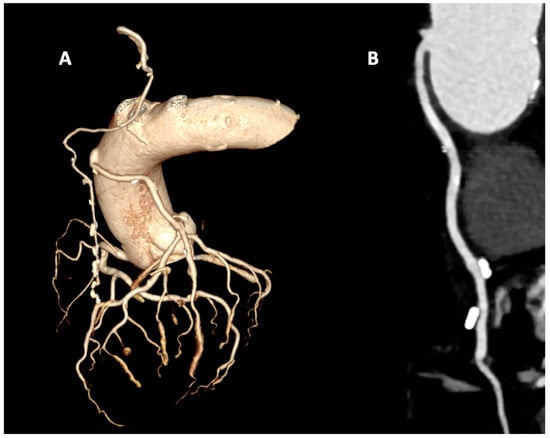

3. Coronary Computed Tomography Angiography